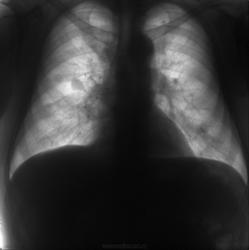

Флюорограммы в динамике. Последние две - прямая и боковая в 2012 г.

Флюорограммы в динамике.

Согласен, наиболее вероятно метастазирование. В 2010 на боковушке, чуть ниже корня уже виден метастаз.